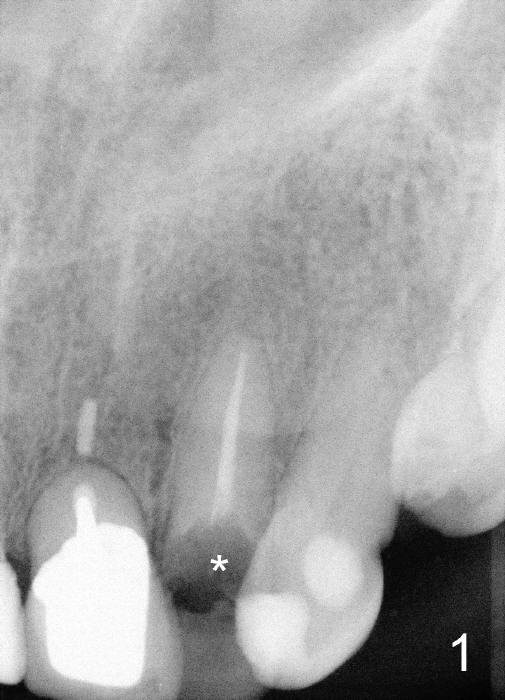

A fifty five year old lady requests implant restoration for the upper left lateral incisor after the crown fractures (Fig.3*). X-ray in Fig.1,2,4 were taken before loss of the crown. The biggest issue is the narrow space of this lateral mesiodistally (Fig.3).